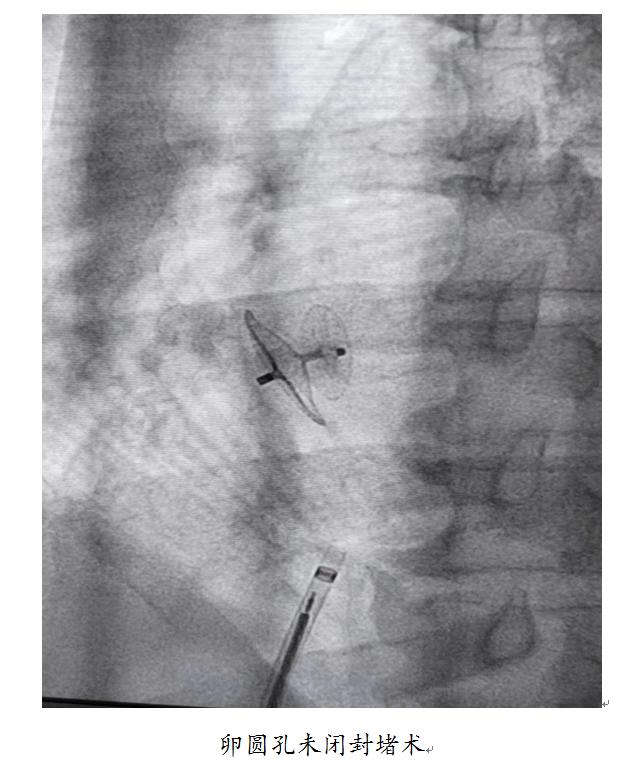

比如,64岁的钱先生,行脑多普勒发泡试验检查提示卵圆孔未闭(固有型,雨帘状),正是因为心脏里面的这个小孔,导致他两次脑梗死,这就是反常栓塞所致(所谓反常栓塞是指,由于卵圆孔未闭,心脏血流存在右向左分流的可能性,静脉形成的血栓进入到体循环从而引起脑梗死)。当医生将病情告知患者后,患者风趣地说道:“浑浊的静脉血流到了清澈的动脉血里”。在苏州高新区人民医院多学科的协作下,心血管内科在张孝忠主任的带领下,为该患者实施了卵圆孔未闭封堵术,在局麻下,仅仅30分钟,就为患者堵住了未闭的卵圆孔;术后8小时,患者就下地活动,他一个劲地夸赞:“我都没有感觉,手术竟然结束了!”

张孝忠主任介绍说,卵圆孔未闭在成人当中十分常见,约1/4的成人存在卵圆孔未闭,对于反复偏头痛、年轻卒中、头颅影像学存在多发缺血性病灶、同时发生体循环及肺循环栓塞等患者应该常规筛查是否存在卵圆孔未闭。目前,发泡试验是发现和诊断卵圆孔未闭的有效方法,包括经胸心脏超声发泡试验、脑多普勒发泡试验、经食道心脏超声发泡试验,目前苏州高新区人民医院均已常规开展。